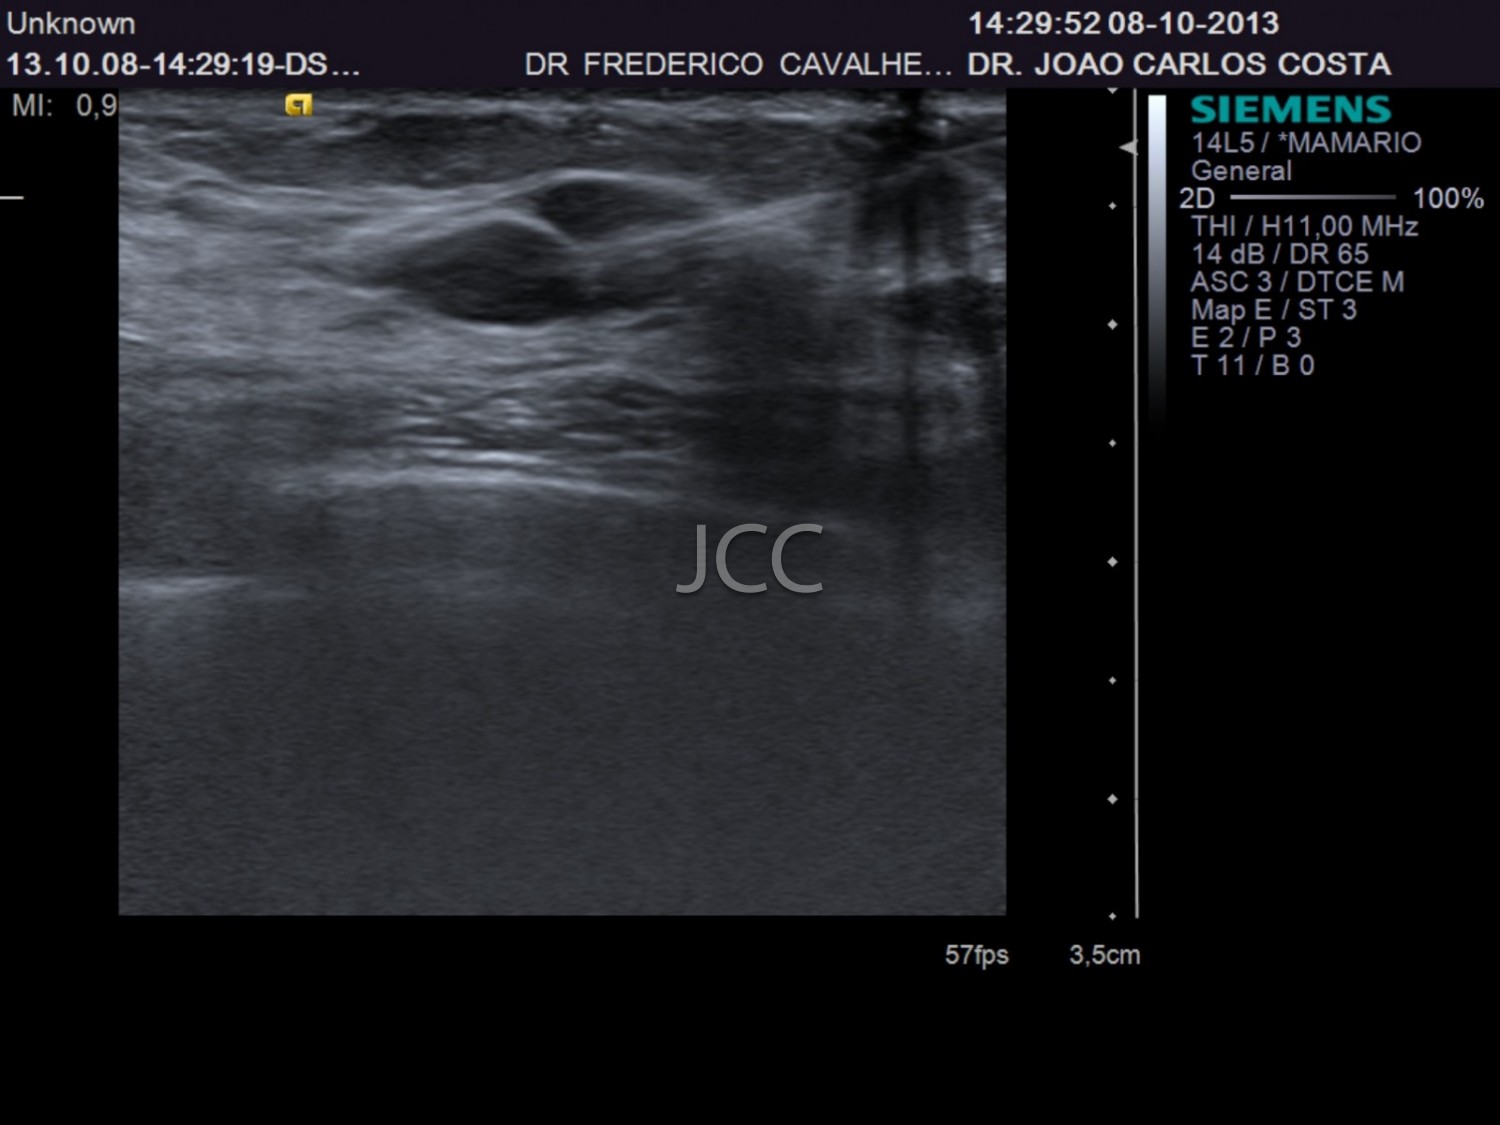

Ecografia - Biópsia por ecografia

A Ecografia constitui um método mais acessível permitindo de modo simples e rápido a avaliação dos órgãos do corpo humano incluindo o fígado, vias biliares, vesícula, pâncreas, rins, bexiga e próstata, bem como órgãos de menores dimensões como a tiróide, parótidas e estruturas musculares.

Constitui uma óptima técnica para guiar a realização de biópsia. Quando associada ao Doppler permite o estudo das estruturas vasculares arteriais e venosas de modo dinâmico.